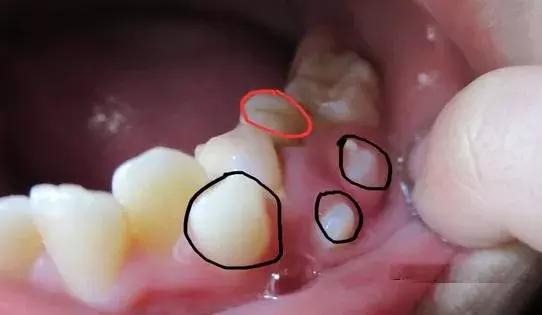

⑵一部分孩子的两个门牙会出现异常的多生牙或者上唇系带附着过低等造成的门牙之间间隙过大的情况,是不会自行消失。多生牙指在牙齿发育时,牙齿的数量比正常情况多。多生牙大多位于两上门牙之间,会影响两个门牙间缝隙的正常闭合,应当及时检查及治疗。